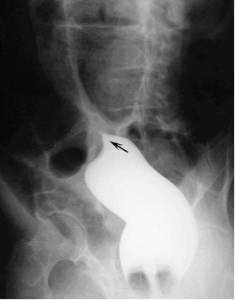

Hình ảnh xoắn đại tràng trên phim Xquang.

Chụp phim Xquang có thể chẩn đoán xác định 60-70% các trường hợp xoắn đại tràng xích-ma với hình ảnh ống hơi hình chữ U lộn ngược chiếm gần hết ổ bụng, hai chân của chữ U hướng về vùng hốc chậu; đại tràng phải giãn và chứa đầy phân; đại tràng xuống bị kéo về đường giữa… Chụp Xquang bụng có thể chẩn đoán xác định hầu hết các trường hợp xoắn manh tràng, với hình ảnh: một “khối hơi” có các đặc điểm của manh tràng. Chụp Xquang đại tràng với Barium vừa có tác dụng chẩn đoán vừa có tác dụng điều trị.